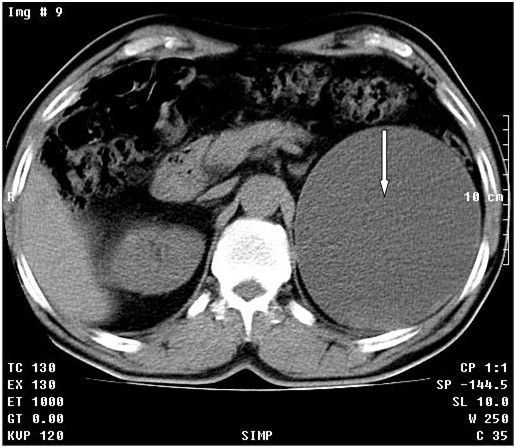

Se realizó tomografía axial computadorizada simple y TAC simple y tomografía con contraste endovenoso y con vistas tardías. Se observó el riñón derecho con dilatación moderada del sistema excretor con posibilidad de quiste asociado (Flecha fina). En el riñón izquierdo se observó proceso expansivo de baja densidad de 13 cm con gruesa cápsula hacia la porción superior del mismo con componente quístico asociado, que provoca retardo en la eliminación del contraste por este lado. (Figuras 1 A, B, C, D flechas gruesas)